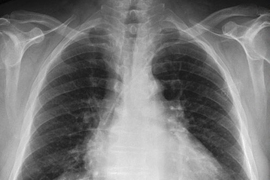

Image of a chest radiograph with color-coded text annotations

An example image-text pair of a chest radiograph and its associated radiology report.

Image courtesy of MIT CSAIL

Getting a quick and accurate reading of an X-ray or some other medical images can be vital to a patient’s health and might even save a life. Obtaining such an assessment depends on the availability of a skilled radiologist and, consequently, a rapid response is not always possible. For that reason, says Ruizhi “Ray” Liao, a postdoc and a recent PhD graduate at MIT’s Computer Science and Artificial Intelligence Laboratory (CSAIL), “we want to train machines that are capable of reproducing what radiologists do every day.” Liao is first author of a new paper, written with other researchers at MIT and Boston-area hospitals, that is being presented this fall at MICCAI 2021, an international conference on medical image computing.

Although the idea of utilizing computers to interpret images is not new, the MIT-led group is drawing on an underused resource — the vast body of radiology reports that accompany medical images, written by radiologists in routine clinical practice — to improve the interpretive abilities of machine learning algorithms. The team is also utilizing a concept from information theory called mutual information — a statistical measure of the interdependence of two different variables — in order to boost the effectiveness of their approach.

Here’s how it works: First, a neural network is trained to determine the extent of a disease, such as pulmonary edema, by being presented with numerous X-ray images of patients’ lungs, along with a doctor’s rating of the severity of each case. That information is encapsulated within a collection of numbers. A separate neural network does the same for text, representing its information in a different collection of numbers. A third neural network then integrates the information between images and text in a coordinated way that maximizes the mutual information between the two datasets. “When the mutual information between images and text is high, that means that images are highly predictive of the text and the text is highly predictive of the images,” explains MIT Professor Polina Golland, a principal investigator at CSAIL.

Liao, Golland, and their colleagues have introduced another innovation that confers several advantages: Rather than working from entire images and radiology reports, they break the reports down to individual sentences and the portions of those images that the sentences pertain to. Doing things this way, Golland says, “estimates the severity of the disease more accurately than if you view the whole image and whole report. And because the model is examining smaller pieces of data, it can learn more readily and has more samples to train on.”